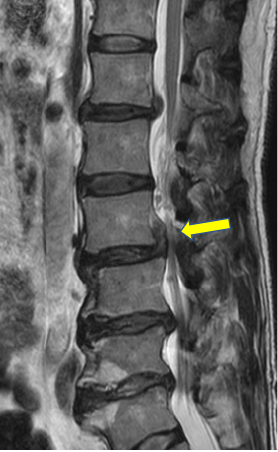

66歳男性 腰椎椎間板ヘルニア(上行性)

腰椎全体の変形があり、腰部脊柱管狭窄症の診断で、他院で治療を受けられていました。

右足の痛みが強く歩行に支障があるため相談にみえられました。2/3腰椎右に椎間板が上方に逸脱して、神経が強く圧迫されていましたので、手術を行いました。

全体に問題がありますが、神経に最も負担になっている部分のみを手術すると負担も少なく、効果的です。